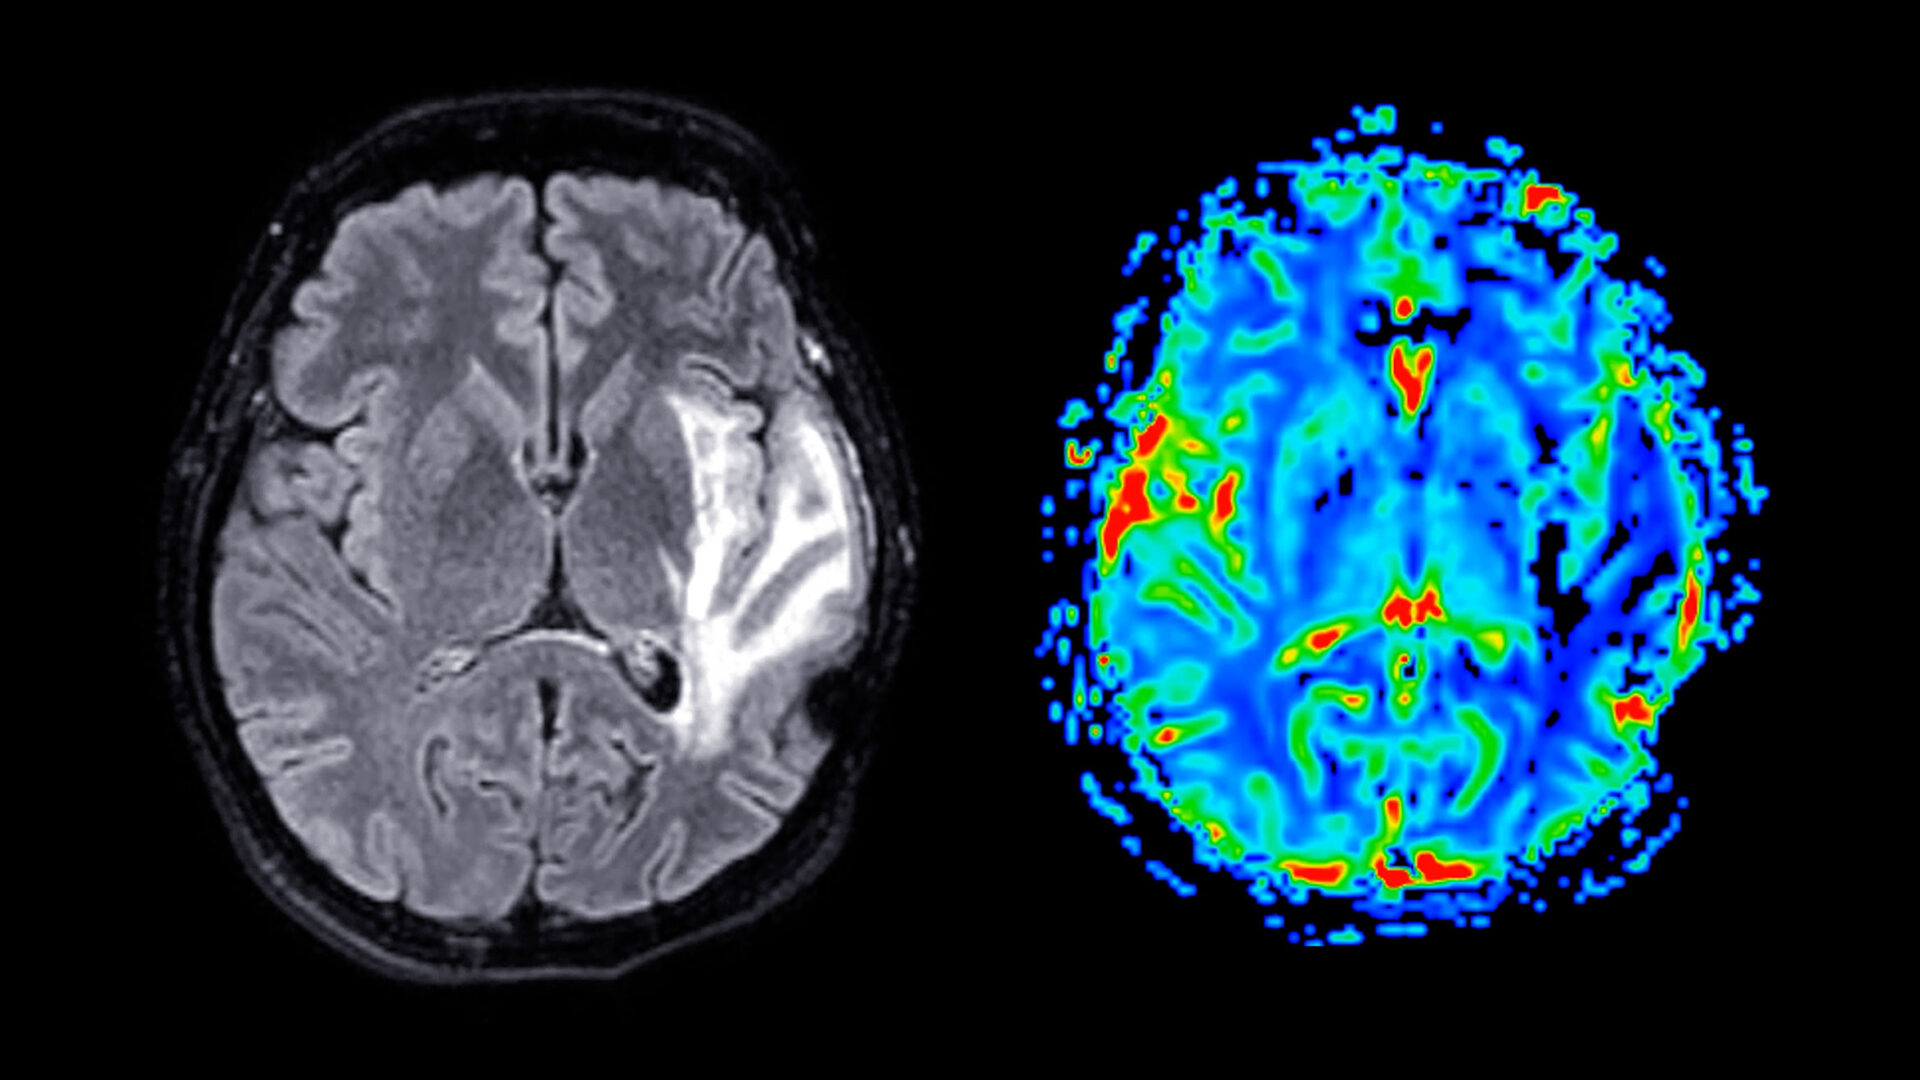

In autopsy analyses, CTE is often marked by shrinking of the brain and the presence of tau protein deposits in sulci near blood vessels.

Researchers found that the football players had shallower left superior frontal sulci on average than their non-football counterparts. Left superior frontal sulci are located on a main groove that runs along the top, front, left side of the brain, which is known to be physiologically affected in CTE.

The study also showed that football players with increasing years of playing experience had wider left occipitotemporal sulci than men who started later or had shorter careers. It is unclear why differences were detected only on one side of the brain and not in the sulci on both hemispheres, the researchers say.

Regarding a potential pathological mechanism, the authors note that models of brain biomechanics suggest that mechanical strain to the brain concentrates, in part, at the depths of sulci. This localized strain may disrupt axonal integrity and trigger the initiation of tau pathology, which, over time, can drive neuroinflammation, neuronal loss, and cortical atrophy, potentially leading to structural changes of sulcal widening and shallowing, as reported in the study.